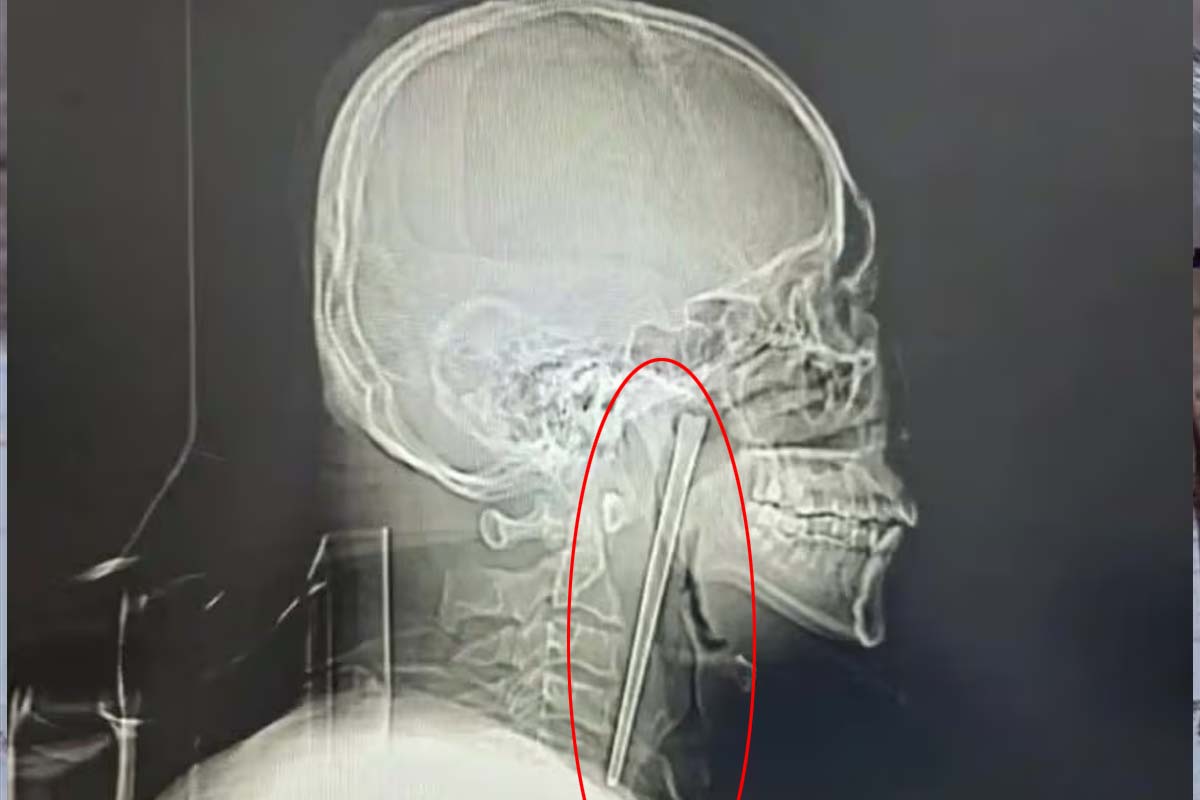

குழந்தைகள் கூட கவனமாக சாப்பிடுவார்களே! என்று நமக்கு நிச்சயம் கேள்வி எழும். குறித்த நபர் மது அருந்திக்கொண்டே நூடுல்ஸ் சாப்பிட்டுள்ளார். அவர் நூடுல்ஸ் சாப்பிடுவதற்கு 12 செ.மீ நீளமுள்ள மெட்டல் சாப்ஸ் ஸ்டிக்கை பயன்படுத்தியுள்ளார்.

திடீரென குச்சியை விழுங்கிய நிலையில், அவை தொண்டையில் சிக்கியுள்ளது. அதனை கழுத்தில் அறுவை சிகிச்சை செய்து எடுக்க வேண்டும் என மருத்துவர்கள் கூறியுள்ளனர்.

இதனால் பயந்து போன குறித்த நபர் 8 ஆண்டுகளாக அப்படியே தொண்டியில் சாப்ஸ் ஸ்டிக்கை வைத்து வாழ்ந்துள்ளார். ஆனால் சமீப காலமாக அதிகமான வலி ஏற்பட்டுள்ளது.

இதனால் மருத்துவமனைக்கு சென்றவர் அங்கு மருத்துவம் மூலம் அறுவை சிகிச்சை செய்து குறித்த சாப்ஸ் ஸ்டிக்கை வெற்றிகரமாக அகற்றியுள்ளனர்.